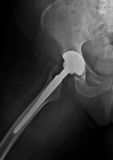

2. Intracapsular fracture of the right hip in a 74-year-old female.

Treatment: Total hip arthroplasty

I. Anteroposterior x-ray pelvis shows the fracture on the right hip II. Anteroposterior x-ray pelvis shows the total hip arthroplasty three months down the line from the operation III. Lateral view hip shows the total hip arthroplasty three months down the line from the surgery